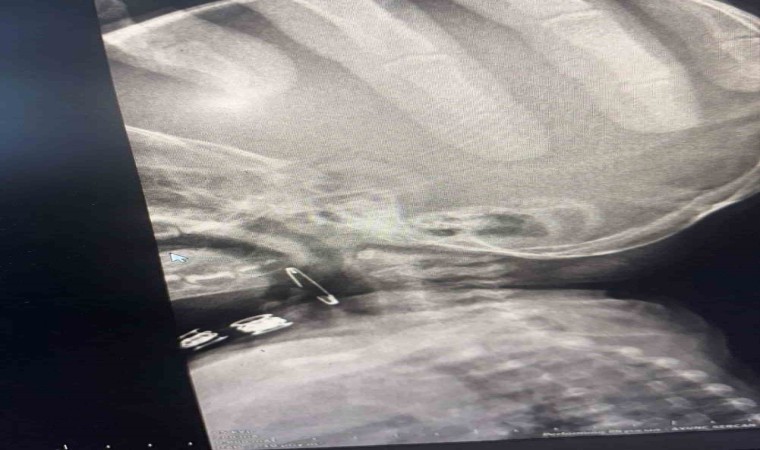

Güroymak ilçesinde 8 aylık bebek, evde bulunan çengelli iğneyle oynarken onu yuttu. Öksürmeye başlayan minik çocuğun, hastanede çekilen röntgen sonucu çengelli iğneyi yuttuğu fark edildi. Güroymak Devlet Hastanesi’nden Tatvan Devlet Hastanesi’ne ambulansla sevki gerçekleşen minik çocuk, Kulak Burun Boğaz Hastalıkları Uzmanı Operatör Dr. Hakan Tuhan tarafından yapılan başarılı operasyonla sağlığına kavuştu. Çengelli iğnenin saplı olduğu soluk borusundan çıkarılan bebek, 2 saatlik gözlemin ardından taburcu edildi.

Konuyla ilgili açıklamada bulunan Kulak Burun Boğaz Hastalıkları Uzmanı Operatör Dr. Hakan Tuhan, “8 aylık bir bebek, Bitlis’in Güroymak ilçesinden tarafımıza danışıldı. Güroymak ilçesinde çekilen röntgen sonucunda çengelli iğnenin soluk borusunun girişinde olduğunu teyit ettik. Yapılan müdahaleler sonucunda çengelli iğneyi çıkardık. Çıkardıktan sonra iki saat kadar gözlem altında tuttuk hastamızı. Daha sonrasında herhangi bir komplikasyonla karşılaşmadık ve sorunsuz bir şekilde taburcu ettik” dedi.